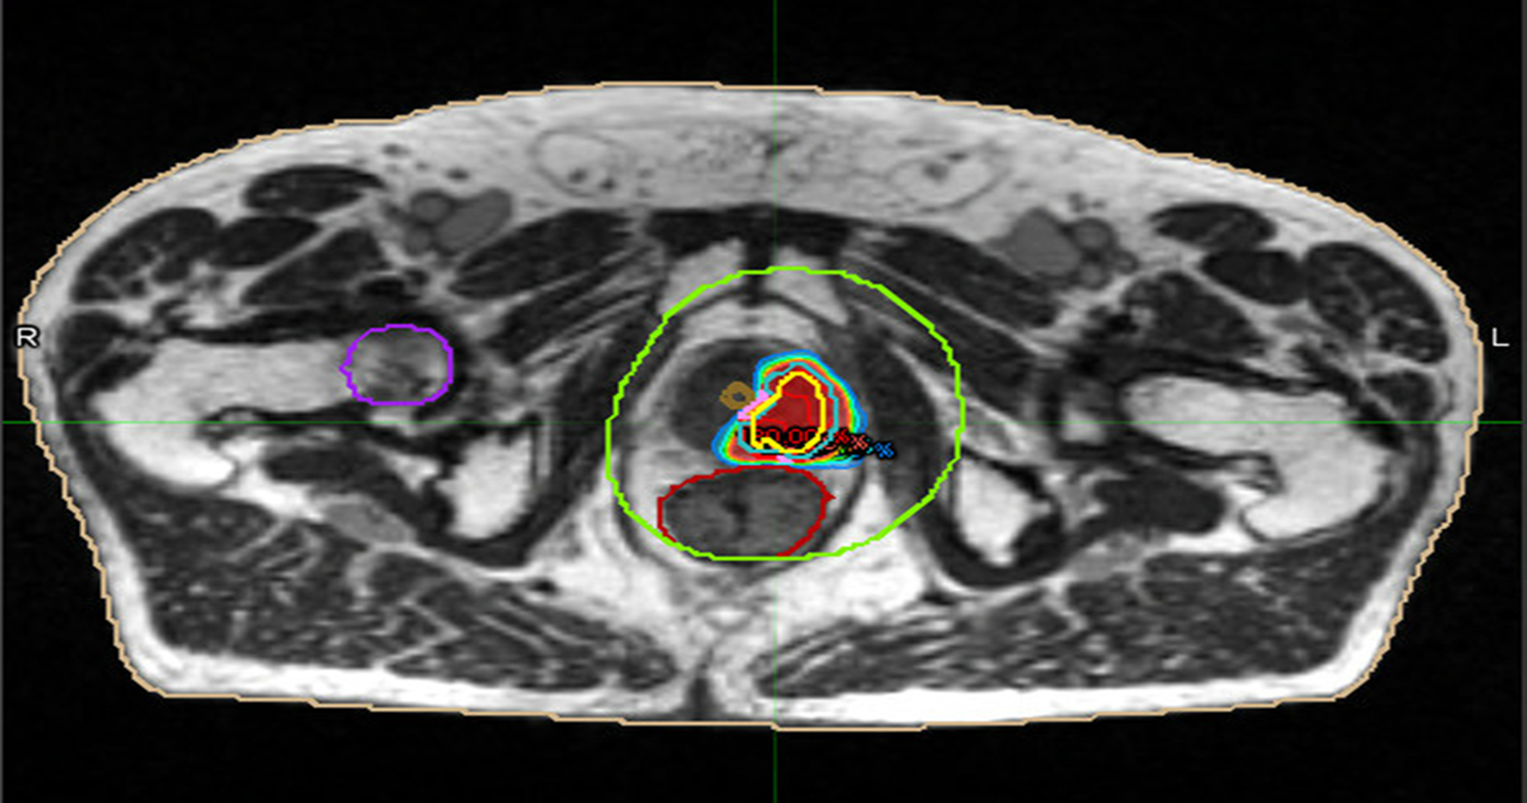

Figure 3: radiotherapy plan axial view

Figure 4: Radiotherapy plan 3D view